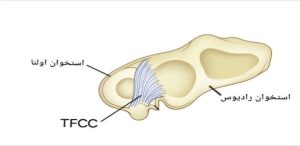

در فضای بین استخوان ساعد (رادیوس و اولنا ) و استخوان های مچ دست (لونیت و تریکوئتروم )فضای خالی وجود دارد ،در این فضا بافت مثلثی فیبری-غضروفی (TFCC) استخوان های ساعد را به استخوان های مچ دست متصل می کند. این ساختار که از رباطها ، تاندونها و غضروف ها تشکیل شده و حالت بالشتک مانندی دارد به قدرت و تثبیت مچ دست کمک می کند( شکل ۱).

شکل۱. در این شکل استخوان های رادیوس و اولنا و TFCC و اتصالات بین آنها نشان داده شده است.